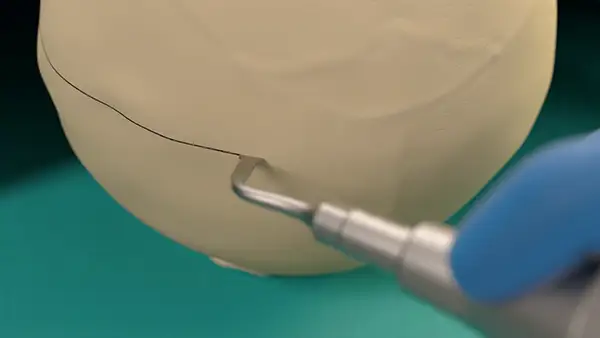

Craniotomy

and craniectomy

Drilling a hole

for dural suspension

Exeptional precision and versatility in bone remodeling

Micrometric cut for minimal bone loss